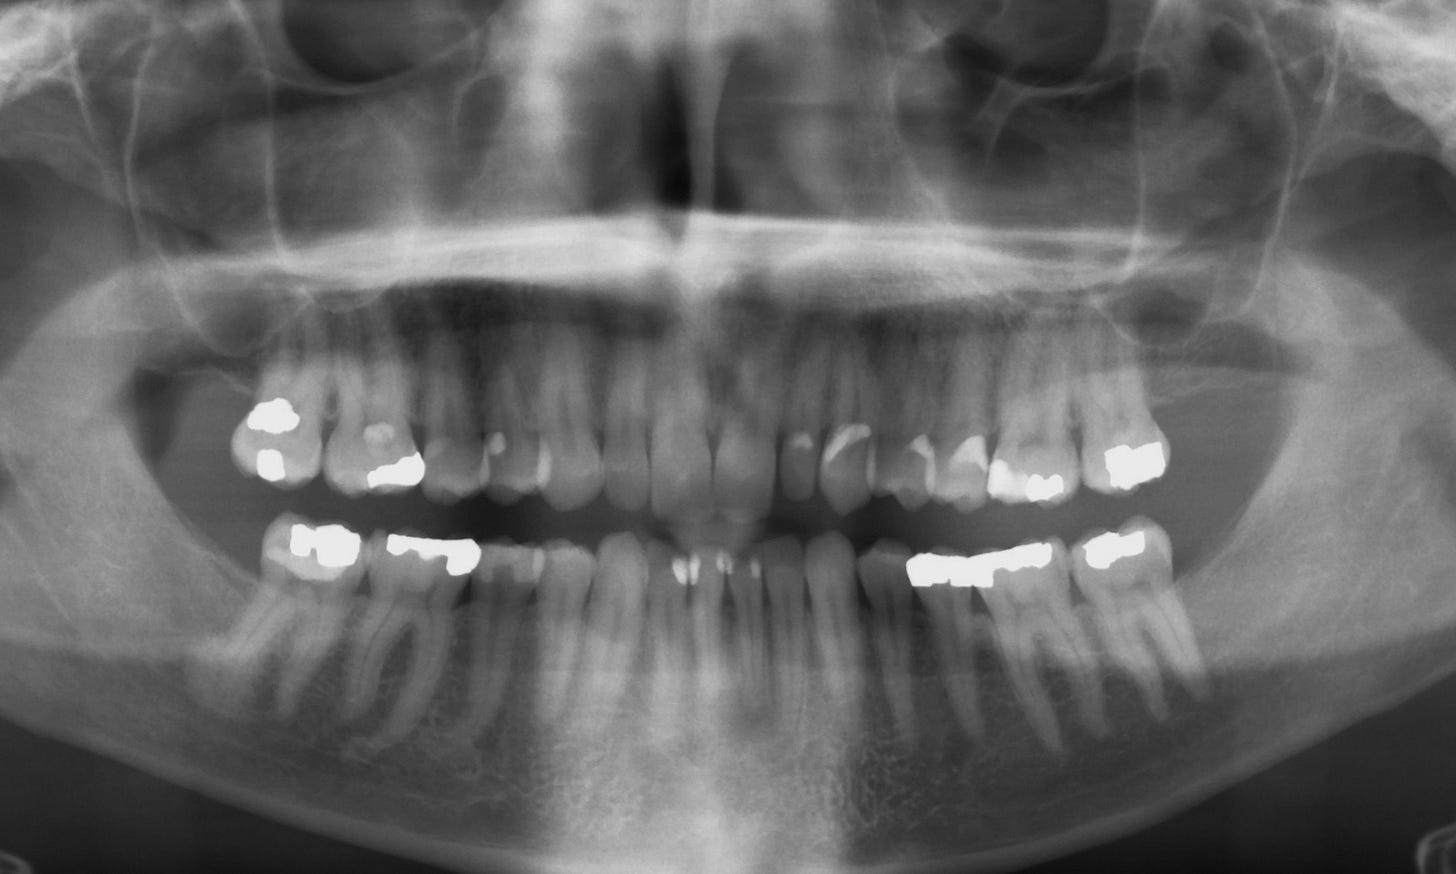

This was bad. Not bad because I missed those obnoxious cleanings where they look at my teeth, tell me it doesn’t look like I’m doing a good job flossing, and then brush my teeth with pumice and dirt, but because something very bad was going in my lower jaw. This time, my routine X-rays showed that I had “a significant amount of bone loss.”

“Wow, you have a significant amount of bone loss in your lower jaw.” They said.

The man told me that I had an abscessed tooth with an infection that went down so deep into my jaw that it was spreading to my other teeth. I was missing a lot of bone in my lower jaw and would probably need at least three root canals, and maybe even four.

In fact, he said, my jaw looked so bad that he recommended I have all four of my bottom teeth pulled and replaced with implants and bone grafts.

We waited for six months; then I scheduled a follow-up appointment with the periodontist. He said it appeared that, in fact, my three remaining teeth were still alive. And that, somehow, the bone had started growing back, which he had not been expecting. And that maybe we only needed to do the one root canal and that’s it. We may be able to save almost everything after all.

So I did, and he told me my three other teeth were still looking good; it appeared the infection had been completely stopped, and my lower jawbone had grown back even more.